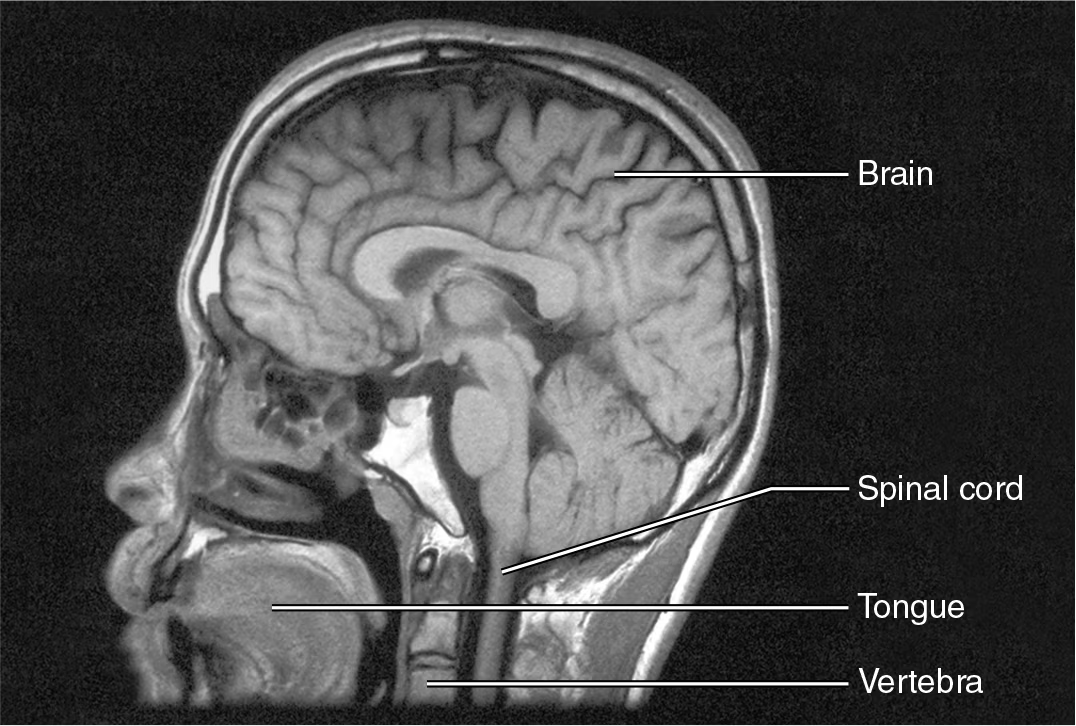

How does Magnetic Resonance Imaging (MRI) work?

it uses powerful magnets and radio waves to image the location of hydrogen atoms in the body, distinguishing body tissues based on water content and producing high-contrast images of soft tissues

What is Magnetic Resonance Imaging (MRI) used for?

imaging of brain, spinal cord and nerves detect abnormalities

fMRI allows visualization of the activity in specific brain regions

What are the drawbacks of Magnetic Resonance Imaging (MRI)?

more expensive and much slower than CT scans

cannot be used in patients with most types of metal implants